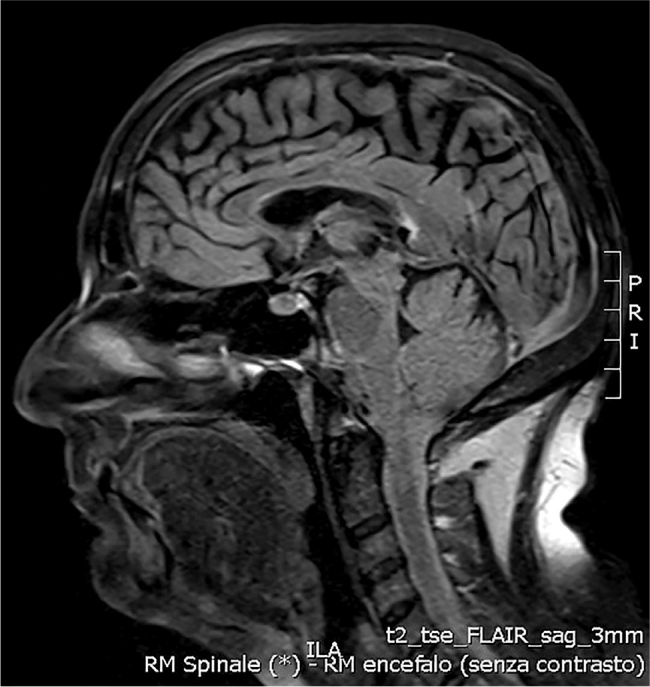

Discussion: An excessive oral intake of folic acid leads to a reduction in the active fraction of vitamin B12 and this decrease exacerbates the deficiency itself. The neurological signs and symptoms of vitamin B12 deficiency are due to demyelination of the posterior and lateral columns of the spinal cord. This patient had been taking folic acid for 30 years and the serum folate value was high. We hypothesise that the high-folate-low-vitamin B12 interaction represents the cause of vitamin B12 depletion in this patient.

Abstract Image